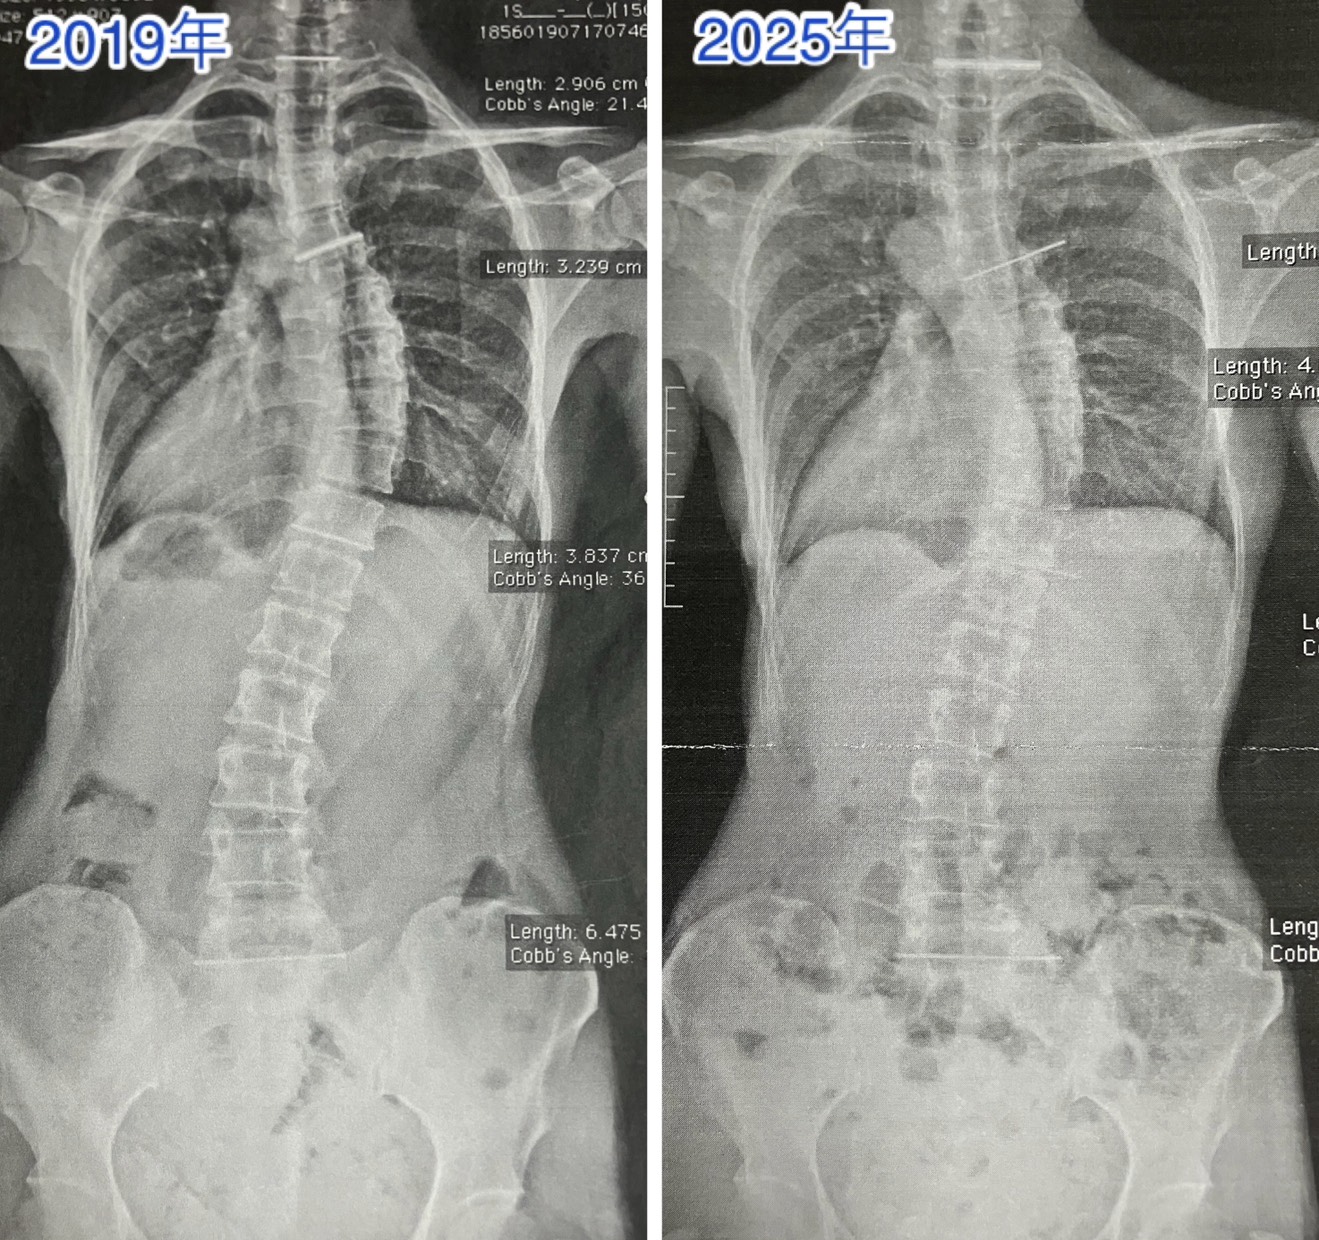

私のレントゲン写真の側弯の変化

これは私のレントゲン写真ですが、ピラティスを開始してから下記のような変化がありました。

【2019年 → 2025年(ピラティス開始前 → 継続後)】

- 胸椎右凸:36.6度 → 34.5度(−2.1度)

- 腰椎左凸:19.2度 → 9.5度(−9.7度)

特に腰椎部分が、大きく歪みが減少しました。

写真を見てもわかる通り、明らかに姿勢が変わっていることがわかると思います。側弯症で歪んでしまったものを完全に真っすぐに矯正することは難しいですが、マンツーマンピラティスでお客様の状態に合わせて体の使い方や呼吸の仕方、動いていないところを動かすなど、専門的な工夫により、これだけの変化を得られました。